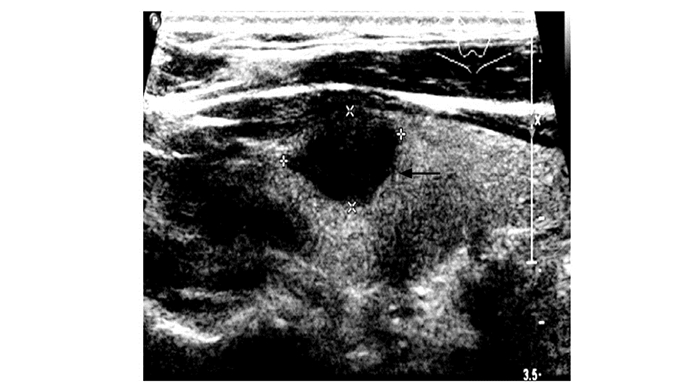

结果  在超声检查可疑恶性的162个甲状腺结节中, 经术后病理证实33个(20.37%)为良性, 其中以结节性甲状腺肿伴钙化或(和)纤维化最多见(12个, 36.36%)。误诊结节中最常见的超声征象为微小钙化(20个), 其他包括结节边界不规则(9个)、纵横比≥ 1(6个)、血流异常(6个)等。

Results  A total of 162 nodules were suspected malignant in ultrasonography, among which 33 (20.37%) were benign based on pathologic results, primarily nodular goiter with calcinosis/fibrosis(12, 36.36%). Microcalcification(20), irregular boundary of the nodules(9), a taller-than-wide shape(6), and abundant and abnormal blood flow(6) were the most common ultrasonographic signs in turn in those misdiagnosed nodules.